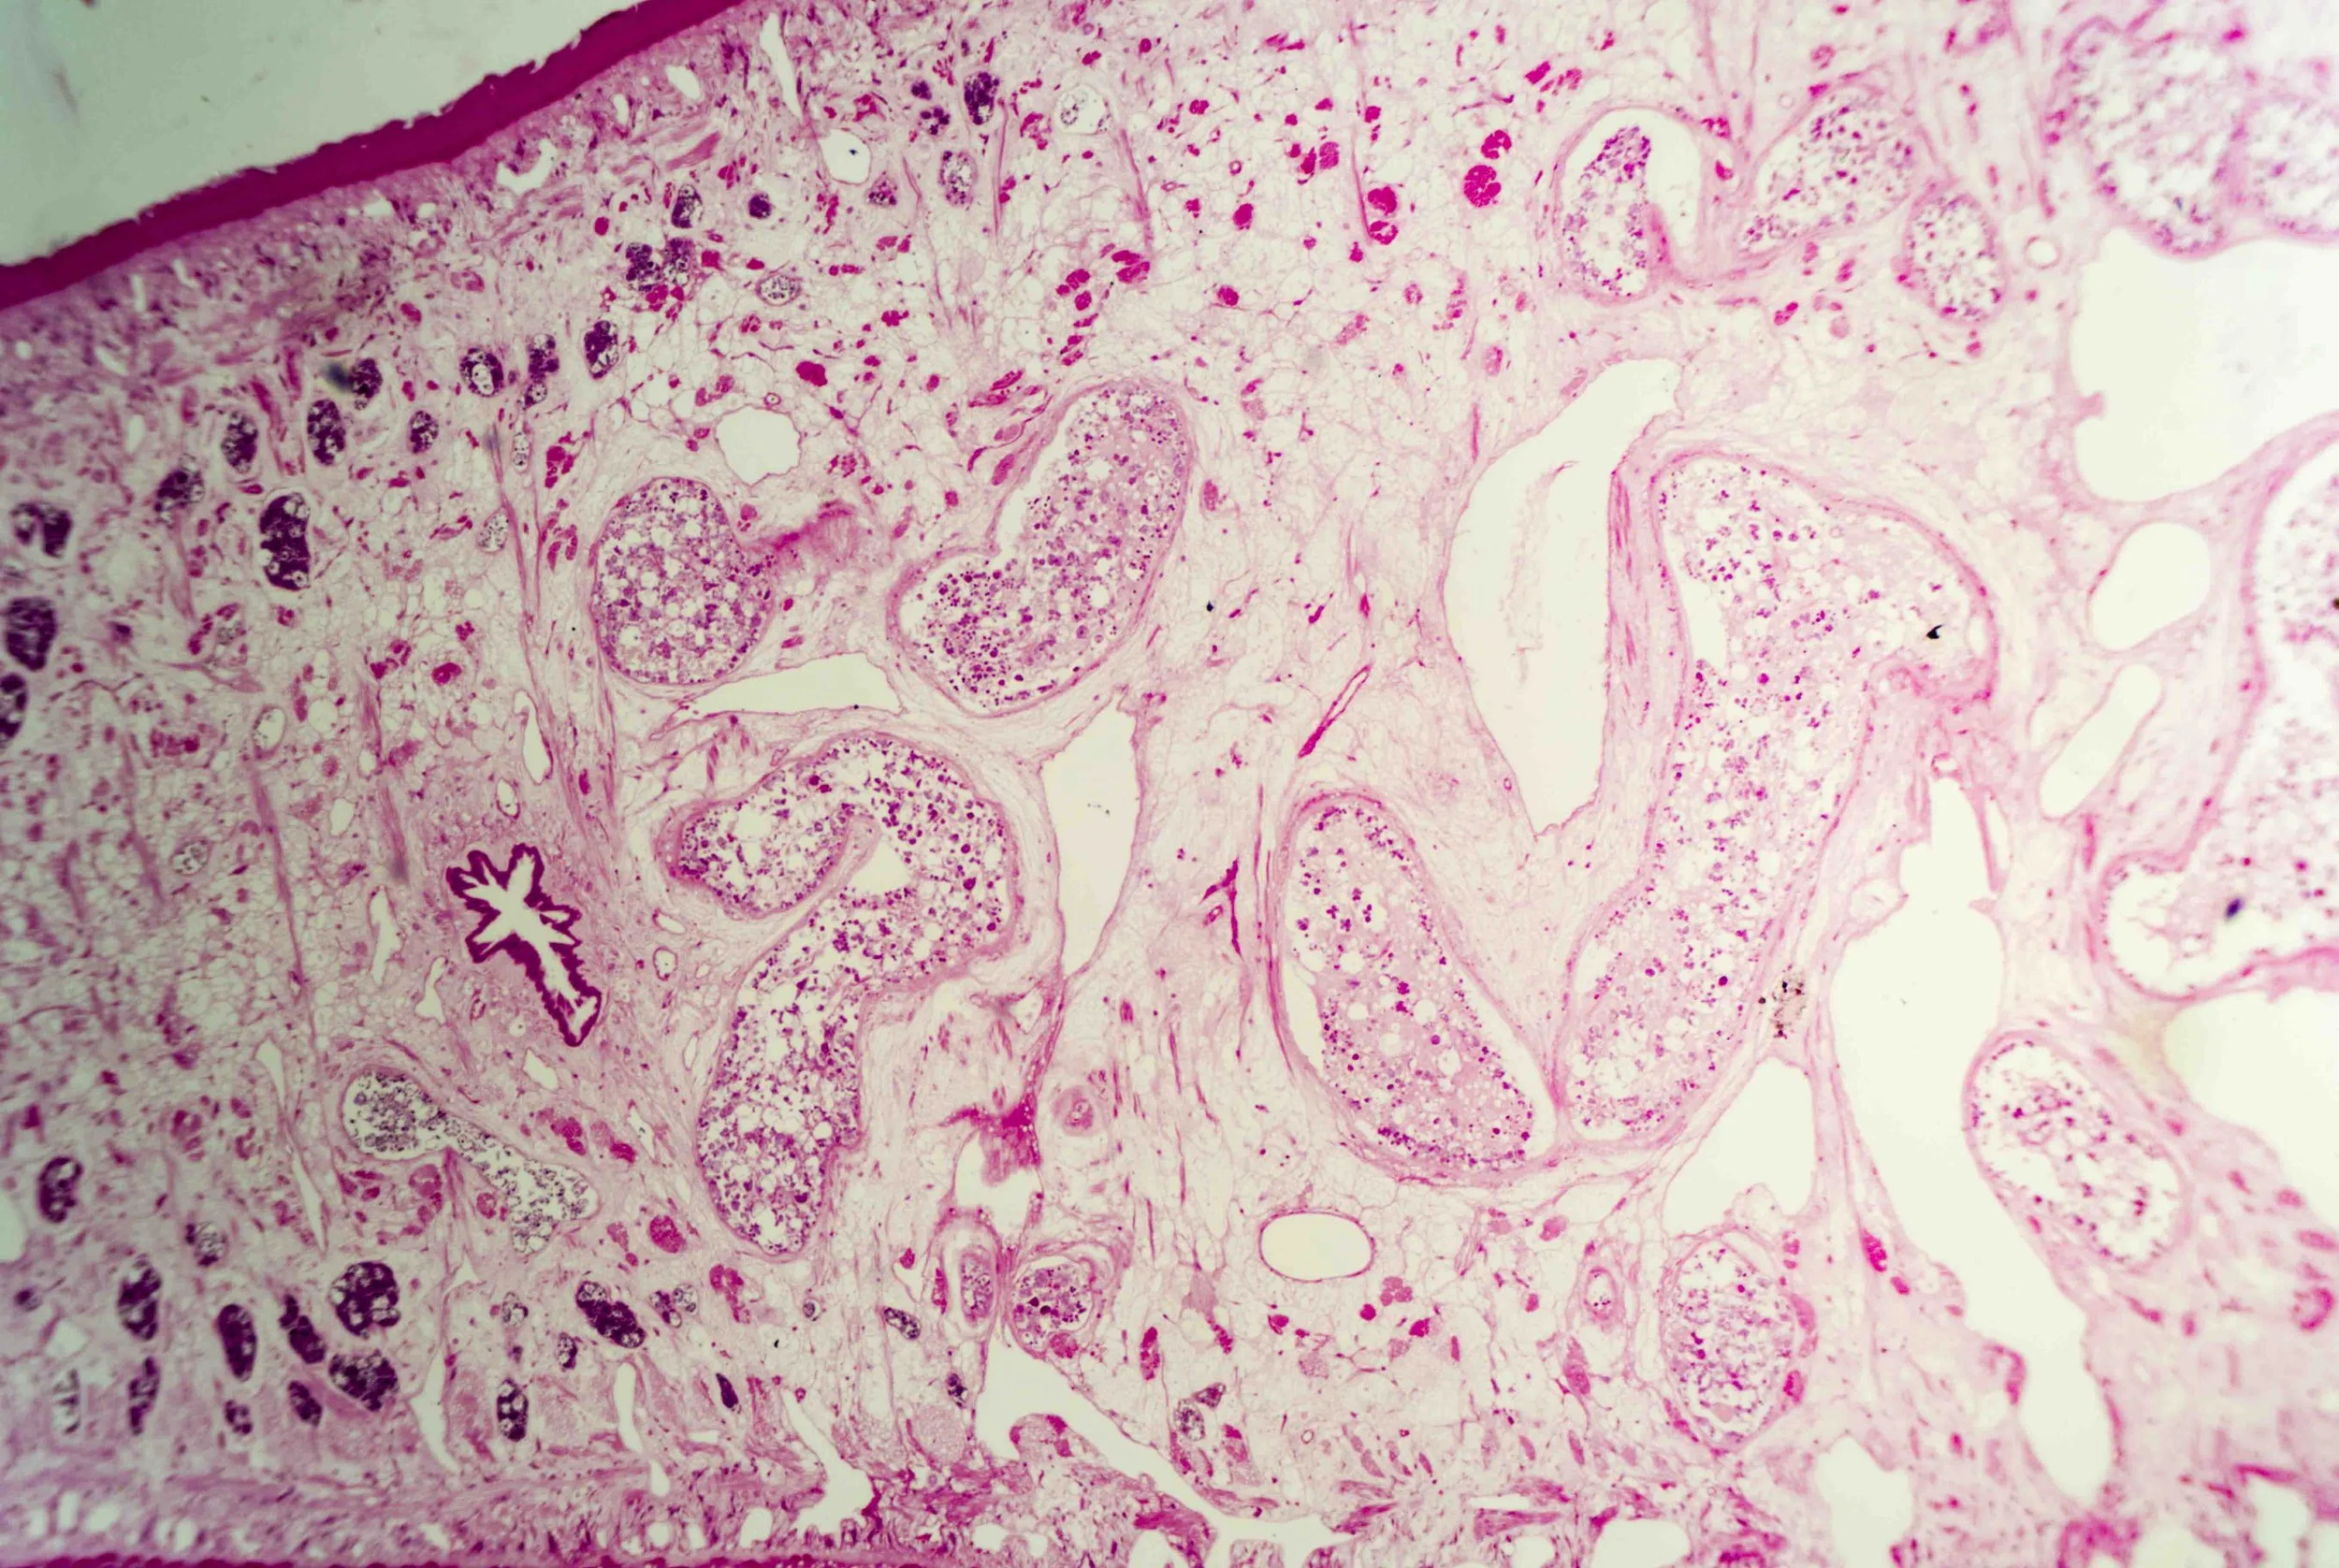

At first glance, a liver fluke is a simple, leaf‑shaped flatworm. Under magnification, however, a cross‑section reveals a labyrinth of chambers and cells, like stained‑glass windows filled with pink and purple mosaics. These sections show the parasite’s densely packed tissues, reproductive organs and digestive sacs nestled within its protective tegument.

The surface of the fluke is wrapped in a syncytial tegument—a scleroprotein‑rich skin enveloped in glycocalyx—that protects the parasite from digestive enzymes and allows nutrient absorption.

Tiny spines on this tegument become more numerous and multi‑pointed as the fluke approaches the bile ducts, helping it anchor and resist the flow of bile.

Liver flukes are hermaphrodites, carrying both male and female reproductive organs. They feed primarily on blood within the host’s liver and bile ductsen.wikipedia.org, and their branched intestine distributes nutrients throughout the body.

Yet there is an eerie beauty in their design. The intricate patterns seen in histological sections hint at the fluke’s complex adaptations—suckers, tegument, branched gut and prolific reproductive tissues—all evolved to exploit its ecological niche.